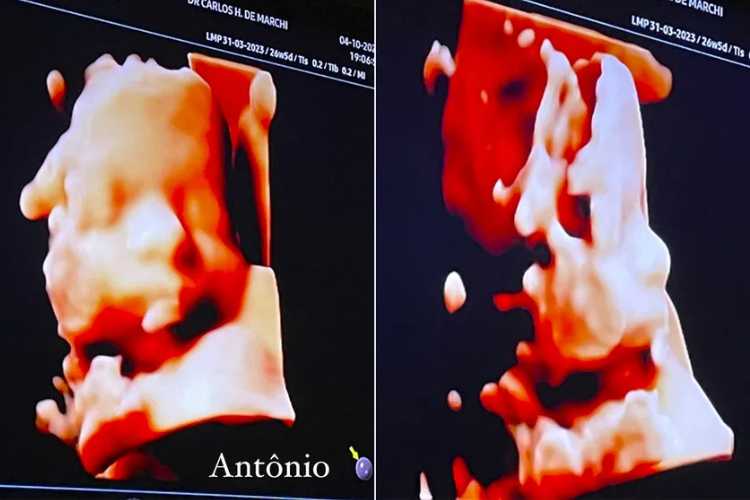

Detalhes do Ultrassom: Conhecendo Álvaro e Antônio

Dado momento, Evans compartilhou com seus seguidores imagens do rostinho adorável de seus gêmeos em seu último exame de ultrassom. Além disso, ela discutiu as dores e desconfortos que tem experimentado na reta final de sua segunda gravidez.